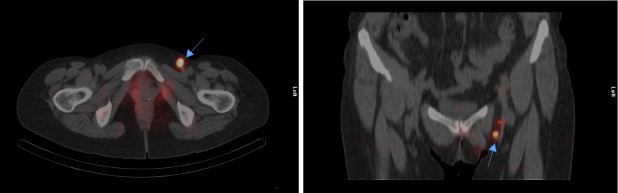

Se realizaron imágenes estáticas planares a los 30 minutos y a las 2 horas tras la inyección del radiotrazador, en proyección anterior y posterior del abdomen y pelvis de 180 segundos cada una, y se realizó una adquisición SPECT/CT de la pelvis a las 2 horas. Posteriormente se marcó con tinta indeleble sobre la piel el lugar donde se localizaba el/los ganglio/s centinela/s, considerándose como tales aquellos que se visualizaron tanto en las imágenes planares precoces como en las tardías, y en el caso de no observarse en las imágenes precoces, aquellos que se visualizaron en la imagen tardía más próximos a la región tumoral (fig. 1). El equipo utilizado fue una gammacámara híbrida de doble cabezal Symbia-T6 (Siemens, Alemania), con colimador de baja energía y alta resolución. Las imágenes estáticas se adquirieron utilizando una matriz de 256×256. Para el estudio tomogammagráfico se utilizó una matriz de 128×128 y se adquirieron 32 imágenes de 20 segundos cada una. La TC se adquirió con una matriz de 128×128, zoom de 1,0, intensidad de 50 mA, energía potencial eléctrica de 110 Kv y un espesor de corte de 5 mm. El procesado se realizó mediante retroproyección filtrada con filtro Butterworth (corte 0,5; orden 5) con un tamaño de píxel de 4,8 × 4,8 mm (fig. 2). Las imágenes fueron interpretadas por 2 médicos nucleares con amplia experiencia en la técnica de la BSGC.